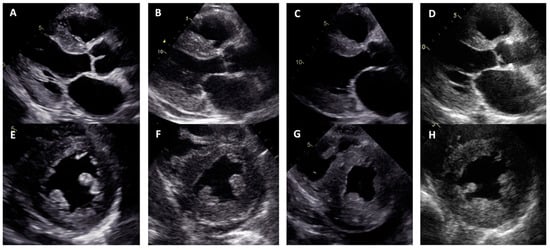

| Proband No. | 1 | 2 | 3 | 4 |

|---|---|---|---|---|

| Zygosity of NM_000371.3:c.302C>T, NP_000362.1:p.(Ala101Val) variant in TTR | Homozygous | Heterozygous | Heterozygous | Heterozygous |

| Sex | Male | Male | Female | Female |

| Age of onset of symptoms (years) | 44 | 74 | 50 | 72 |

| Age at diagnosis (years) | 49 | 77 | 57 | 74 |

| NYHA class of heart failure | III | III | III | III |

| Positive family history | Mother at an older age and aunt on mother‘s side had heart disease | Brother had heart disease | Mother had heart disease, grandmother on mother‘s side had sudden death | Mother and brother died of stroke at an older age |

| Low QRS voltage | - | + | + | + |

| Pseudoinfarct pattern on ECG | - | - | - | - |

| Conduction disturbances | RBBB, LAFB | LBBB | - | LBBB |

| Atrial fibrillation | - | + | + | - |

| LV hypertrophy | Concentric | Concentric | Concentric | Concentric |

| Maximal wall thickness (mm) | 13 | 21 | 14 | 19 |

| LVEF (%) | 67 | 10 | 55 | 40 |

| Restrictive LV filling pattern | - | + | + | + |

| Increased RV wall thickness | + | + | - | + |

| Pericardial effusion | - | + | - | - |

| Cardiac MRI LV hypertrophy | Asymmetric (predominantly in transventricular septum) | Symmetric | Symmetric | Symmetric |

| Cardiac MRI maximal wall thickness (mm) | 16 | 19 | 14 | 20 |

| Cardiac MRI LVEF (%) | 77 | 45 | 50 | 44 |

| Cardiac MRI LGE | Midmyocardial LGE in LV septum and inferior wall | Diffuse subendocardial LGE in LV and RV | Diffuse midmyocardial LGE in LV and RV | Diffuse subendocardial LGE in LV and RV |

| 99mTc-PYP bone scintigraphy | Grade 0 | - | - | Grade 3 |

| Histological confirmation | Amyloid deposits, likely non-specific reaction to transthyretin on immunohistochemistry in bone marrow trepanobiopsy and endomyocardial biopsy | TTR amyloid deposition in adipose tissue biopsy | TTR amyloid deposition in endomyocardial biopsy | - |

| NT-proBNP (pg/mL) * | 474 | 11401 | 3368 | 2471 |

| Troponin I (ng/L) * | 111 | 95 | 65 | 45 |

| Polyneuropathy | + | - | - | + |

| Chronic kidney disease | - | + | + | - |

| Gastrointestinal manifestation | + | + | - | - |

| Carpal tunnel syndrome | - | - | + | + |

| Biceps tendon rupture | - | NA | - | - |

| Follow-up after diagnosis (years) | 3 | 2 | 3 | 1 |

| Outcome | Death at age 52 due to pneumonia complications | Death at age 79 due to colon adenocarcinoma | Death at age 60 due to heart failure decompensation | Death at age 75 due to heart failure decompensation |

| Family segregation analysis | NA | Variant identified in phenotypically negative 47-year-old daughter | Variant identified in phenotypically negative 33-year-old daughter | NA |